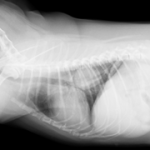

症例:10歳 チワワ 避妊雌

主訴:最近咳をたびたびしており、他の病院にてレントゲン検査をしたところ肺の右後葉に腫瘍が認められたため、手術のため当病院を紹介されて来院されました。

当病院のレントゲン検査でも肺腫瘍が認められたため、咳の症状も腫瘍によるものと診断、飼い主様の希望により肺腫瘍摘出手術を行いました。